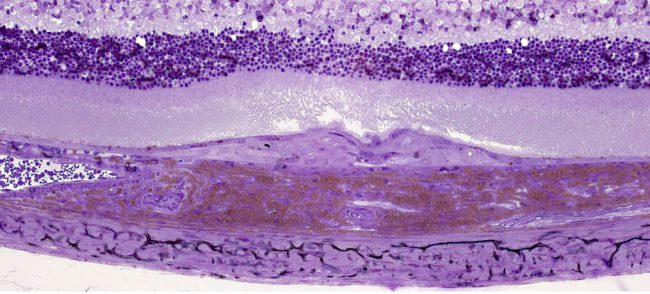

- Photoreceptor toxicity assessment

- Retinal Pigment Epithelium (RPE) toxicity assessment

- Photoreceptor toxicity assessment

- Retinal Pigment Epithelium (RPE) toxicity assessment